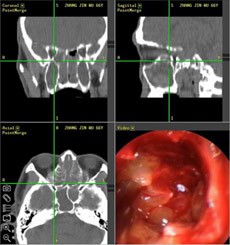

【典型案例】反复手术切息肉 复发导致嗅觉减退5年之久

张先生家住兰州,是典型的鼻窦炎患者,经常会出现鼻塞、流脓涕、头痛、等症状,去过多家医院,治疗结果并不理想,复发不说,到现在张先生的嗅觉已经严重减退,味道都快闻不出来了。

经推荐,跨省来到西安新城中大耳鼻喉医院耳鼻喉科治疗,入院后,经医生诊断并推荐使用“”,在鼻内窥镜的帮助下切除鼻息肉,术后经过10天后复诊并无复发现象。

(图为:鼻窦炎患者治疗现场) (图为:鼻窦炎治疗图谱)

[原理阐述]: “”技术以“CT片检查”和“STORZ鼻内窥镜”精准定位,借助“美国美敦力微创切割动力系统”和“美国杰西微创手术消融系统” 精确“扫净”四对鼻窦炎症,避免“漏诊盲区”、迁延其它鼻窦复发;同时功能性鼻腔术后修复和绿色技术,轻松清除额窦、上颌窦、筛窦和蝶窦等合并症,迅速恢复鼻部功能,治疗恢复期比同等手术缩短三倍,被称为“多窦一清”高端技术。

优势1,精确定位: “功能性鼻内窥镜系统”自带的冷光源的亮度相当于无影灯20倍,清晰的视野使治疗达到更精细的效果,3.5mm的小孔可将病变组织放大数倍,并将同步拍摄到的影象传送到相应的的电脑屏幕上,患者病变部位可被医生一览无余,可告别过去盲目凭手感和经验操作的“盲人摸象”时代。